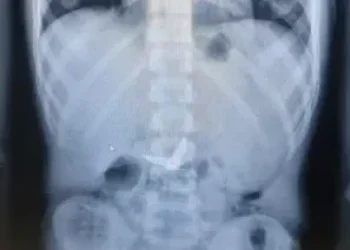

לפי בית החולים, הילד, י', הגיע לחדר המיון בשעות הלילה המאוחרות כשהוא מלווה בהוריו, לאחר שסיפר כי בלע בטעות את המספריים. בצילום רנטגן שבוצע מיד עם קבלתו, התברר כי הלהבים נצפו כשהם פתוחים - בתוך הקיבה. בשל הסיכון המיידי לחתכים ופציעות פנימיות, זומנו במהירות לצוות הרפואי מומחים מתחומי כירורגיית ילדים, גסטרואנטרולוגיה, ואנדוסקופיה, בהם ד"ר אורן לדר, המתמחה בפרוצדורות אנדוסקופיות בילדים.

"מיד לאחר שהילד הורדם כהכנה לניתוח חירום, ערכנו צילום נוסף כדי לאתר את המיקום המדויק של המספריים", מסבירה ד"ר אסתר אורלינסקי-מאייר, רופאה בכירה בגסטרואנטרולוגיה ילדים. "להפתעתנו, ראינו שהמספריים נסגרו מעצמם - דבר שהפחית באופן משמעותי את הסיכון לקרעים ופגיעות פנימיות. הם כבר לא היו בקיבה, אלא התקדמו לעומק המעי הדק".